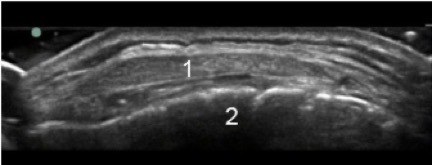

Knee Infrapatellar Tendon Transverse Image

Infrapatellar Tendon

Tibia